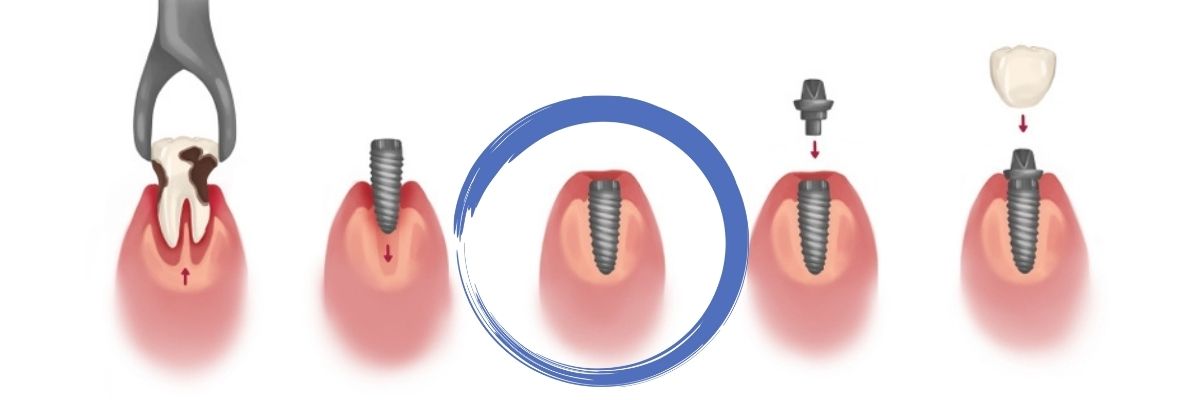

The objective of a dental implant is to place a titanium screw into your jawbone. These titanium screws are surface treated to allow it to fuse and form anchorage (osseointegration) into your jawbone under all normal conditions of oral function. Above this titanium screw lies another screw attachment which allows your implant crown or prosthesis to attach on top of.

When the sterile titanium screw is surgically inserted into the jawbone, the titanium oxide (TiO2) layer on its surface provides an area to which mineralizing bone matrix can attach. Once the implant is introduced into the jawbone, proteins from the patient’s blood are exposed to the surface almost immediately. The body recognizes the implant as its own rather than a foreign body, leading to osseointegration.